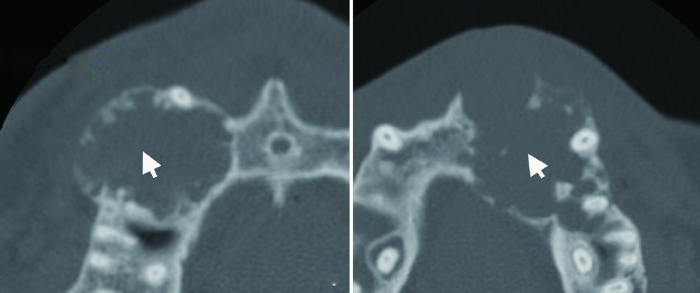

图1

促结缔组织增生型成釉细胞瘤的边界形态特征

Figure 1

The boundary features of DA

A-B, DA shows scalloped shape with short sclerosed border on axial CT images (white arrows); C, Ill-defined border, infiltration into surrounding bone (white arrow) and locally destroyed cortex can be observed in DA; D, DA shows as solid mass on CT (black arrow).